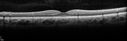

33 year old He noticed a new flash in the left eye. The flash started about 2 hours prior to the photos and he still notices it. The flash is in the center of the vision. The vision is not blurred. It's hard to tell because of the dilation. VA 20/12 OD and 5/200 OS. The vision remarkably improved to 20/16 within 1 month in the left eye. Blood tests showed a protein C deficiency.

Central retinal artery and vein occlusion - Protein C Deficiency 33 year old male406 views33 year old male with vision loss for 3 hours. VA 20/12 right eye, 5/200 left eye. He has a protein C deficiency. The left eye recovered vision in about 1 month to 20/16. FA shows very slow recirculation time.     (0 votes)